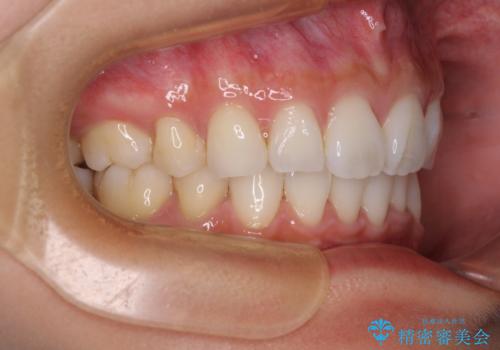

- 飛び出した前歯を気にして来院された患者様です。

口元を引っ込めるために上下左右の第一小臼歯4本を抜歯することとしました。

途中妊娠と出産がありましたが、予定よりも早く治療を終えることができました。